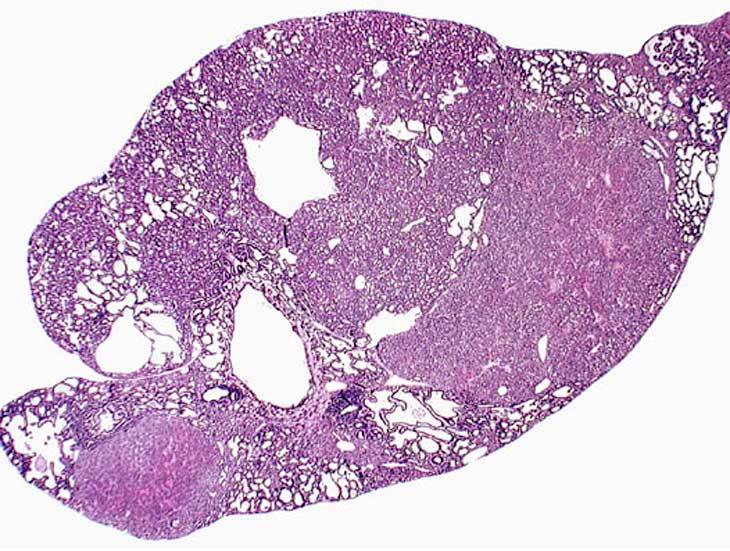

Areas of ductular formation and bile duct proliferation can be extensive in the livers of 3-week old AL-TAg x AL-myc mice.

By 4-weeks of age much of the liver is replaced by areas of ductular formation, cholangial neoplasms, and hepatocellular neoplasms in AL-TAg x AL-myc mice.